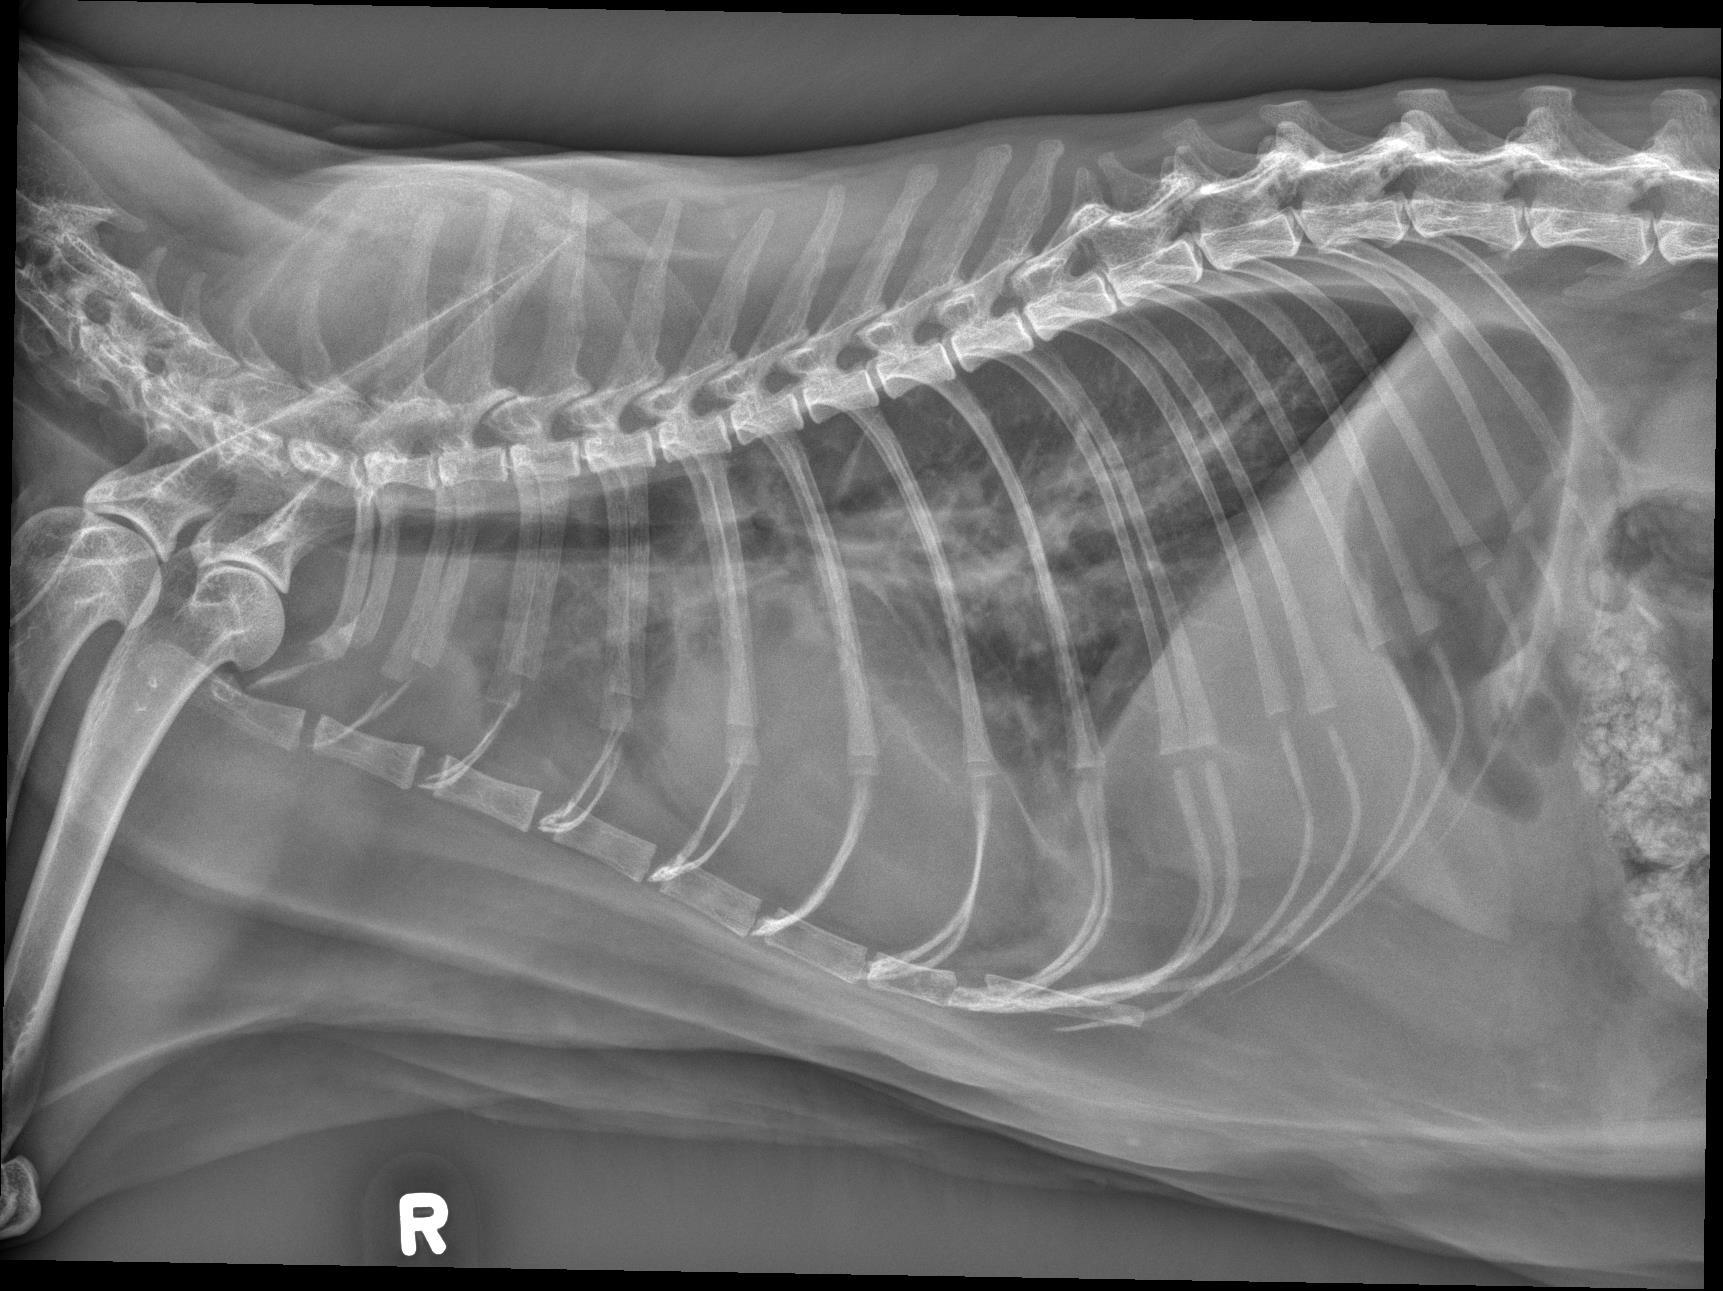

The cardiac silhouette is moderately to severely enlarged occupying greater than 2/3 the height of the thoracic cavity and almost the entire width of the thoracic cavity on the ventrodorsal radiograph. The right cranial lobar pulmonary vein is mildly enlarged compared to the corresponding artery. The pulmonary arteries are enlarged and mildly tortuous. There is a mild, diffuse unstructured interstitial to bronchointerstitial pulmonary pattern.

There is a small volume of fluid in the pleural space of both hemithoraces which widens the pleural fissures. The cranial mediastinum is widened on the ventrodorsal radiograph and there is a focal, rounded, soft tissue opaque convexity immediately dorsal to the second sternebra. There is a small volume of incidental gas within the intrathoracic esophagus.

Severe cardiomegaly in conjunction with the enlarged right cranial lobar vein, pleural effusion and diffuse unstructured interstitial pulmonary pattern is most concerning for congestive heart failure from underlying cardiomyopathy and/or fluid overload. Echocardiography is recommended for further evaluation. The mild tortuosity of the pulmonary arteries may be a patient variant or represent a component of cardiovascular disease (vs. pulmonary hypertension). – The soft tissue convexity immediately dorsal to the second sternebra may represent an enlarged sternal lymph node or loculated pleural effusion.